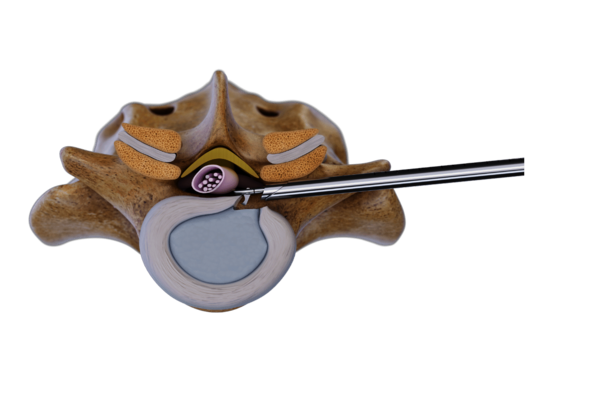

Trans-/extraforaminale Technik

Diese Technik nutzt das Foramen intervertebrale als Zugang zur Pathologie. Der Zugang wird unter Röntgenkontrolle mit einer Punktionskanüle geführt, gefolgt von der Dilatation und dem Einführen der Arbeitshülse.

Der Eingriff erfolgt unter kontinuierlicher Spülung mit hochauflösender endoskopischer Bildgebung. Spezialisierte Instrumente wie Zangen, Fräser und Stanzen gewährleisten einen effektiven und präzisen Eingriff.